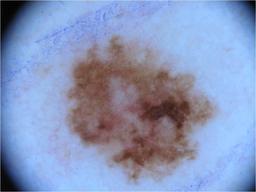

{

"age_approx": 30,

"anatom_site_general": "anterior torso",

"concomitant_biopsy": false,

"diagnosis_1": "Benign",

"diagnosis_2": "Benign melanocytic proliferations",

"diagnosis_3": "Nevus",

"diagnosis_4": "Nevus, Atypical, Dysplastic, or Clark",

"diagnosis_5": "Nevus, Dysplastic",

"image_type": "dermoscopic",

"melanocytic": true,

"sex": "female"

}